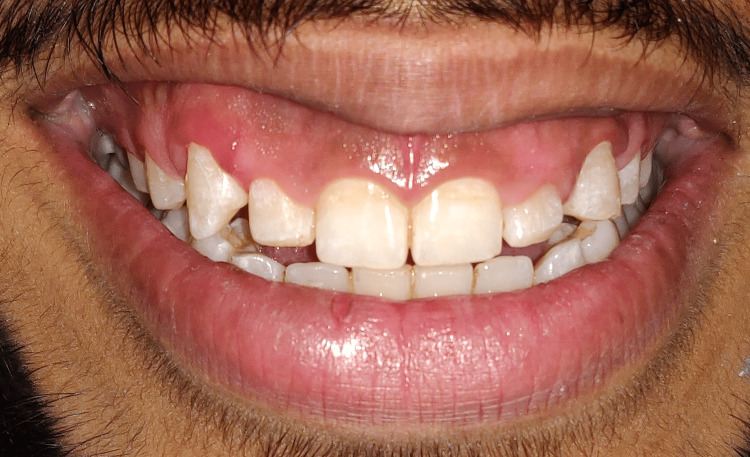

A 27-year-old male patient visited the outpatient Department of Periodontics and Implantology, Sharad Pawar Dental College (DMIMS [DU]) with the chief complaint of a gummy smile and improper aesthetics. The patient provided a past orthodontic treatment history for closing gaps. Following an extraoral and intraoral examination, the patient was evaluated to make the proper diagnosis and develop a treatment plan. Following extraoral assessment, it was noticed that the patient had competent lips at rest, average lip length and mobility, and a standard facial height without any vertical maxillary excess, as indicated in Figures 1, 2.

Figure 1. Pre-operative view depicting patient smile on day 1.

Figure 2. Intra-oral examination depicting the hard and soft tissues.